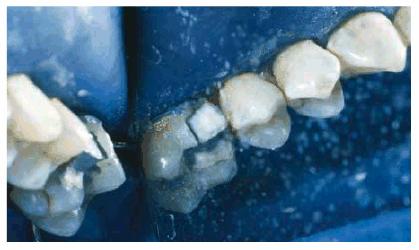

Figure 16-8A and B: Gray stain on lateral incisor (A) is a result of an amalgam restoration on the lingual surface of the tooth (B).